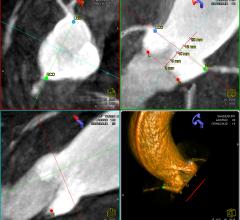

February 16, 2012 — Siemens Healthcare received clearance from the U.S. Food and Drug Administration (FDA) for syngo Aortic ValveGuide, an integrated image processing software that helps cardiologists and cardiac surgeons prepare and perform transcatheter aortic valve replacement (TAVR).